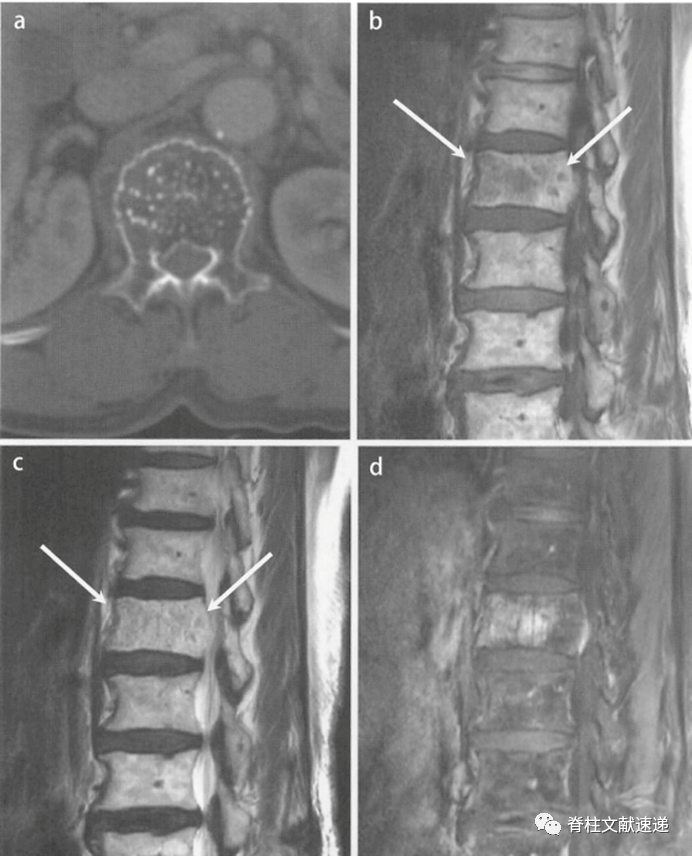

脊膜瘤,最容易被忽视的椎管内肿瘤

为了确诊秦阿姨具体是什么肿瘤,贾栋院长对秦阿姨再次做了详细的腰椎